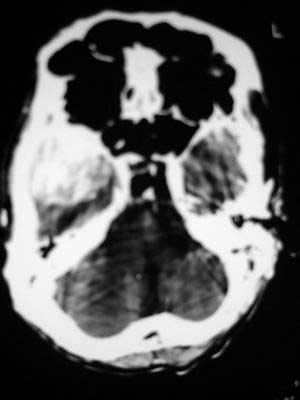

水肿非常明显,侧脑室左移非常明显,平扫病灶稍高密度。

肿瘤位于中颅窝,宽基底与颞骨或蝶骨大翼相连,平扫呈稍高密度,增强后均匀明显强化,肿瘤周围水肿明显,中线结构移位。我认为是脑膜瘤,其压迫大脑中浅静脉,导致静脉回流受阻,引起阻塞性脑水肿。

右侧中颅窝见类圆形的密度增高影(大小待定),增强后均匀明显强化,肿块周围环绕低密度的水肿带,脑中线移位。脑膜瘤可能性大,胶质瘤不能除外;脑水肿。